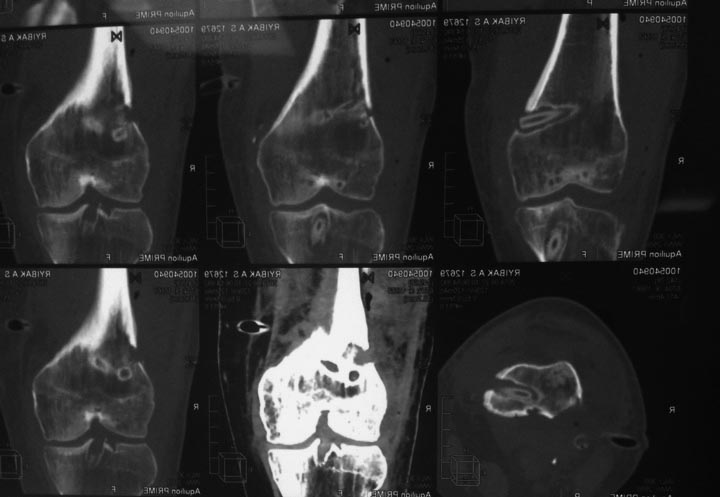

КТ после операции.

Есть остеопороз, но явного остеомиелита не наблюдается.